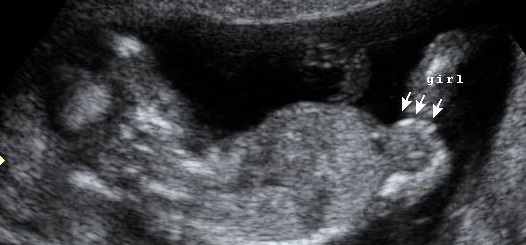

Kiddo wouldn't cooperate and give that sagittal crown to rump shot bc of position, but here are some skull/back/feet shots...

Probably the skull theory is going to be the best indicator for this one...ugh I wish baby would have cooperated, but the good news is baby is on the left side!!